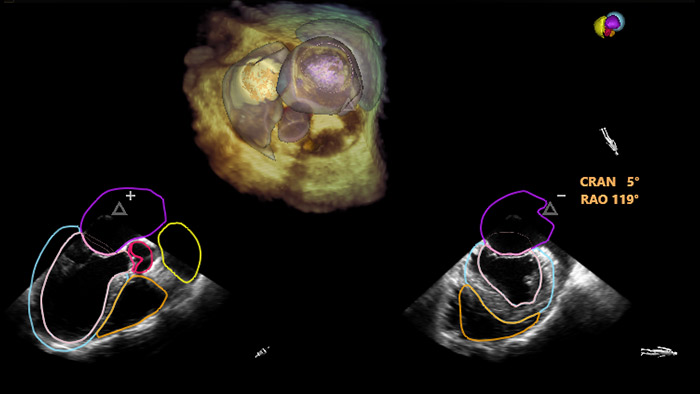

Segmentation de modèle 3D EchoNavigator

Optimisation de la vue de la valve mitrale avec les modèles cardiaques EchoNavigator

Optimisation de la vue de la valvule tricuspide avec les modèles cardiaques EchoNavigator

Visualisation des valves mitrale et aortique avec les modèles cardiaques EchoNavigator